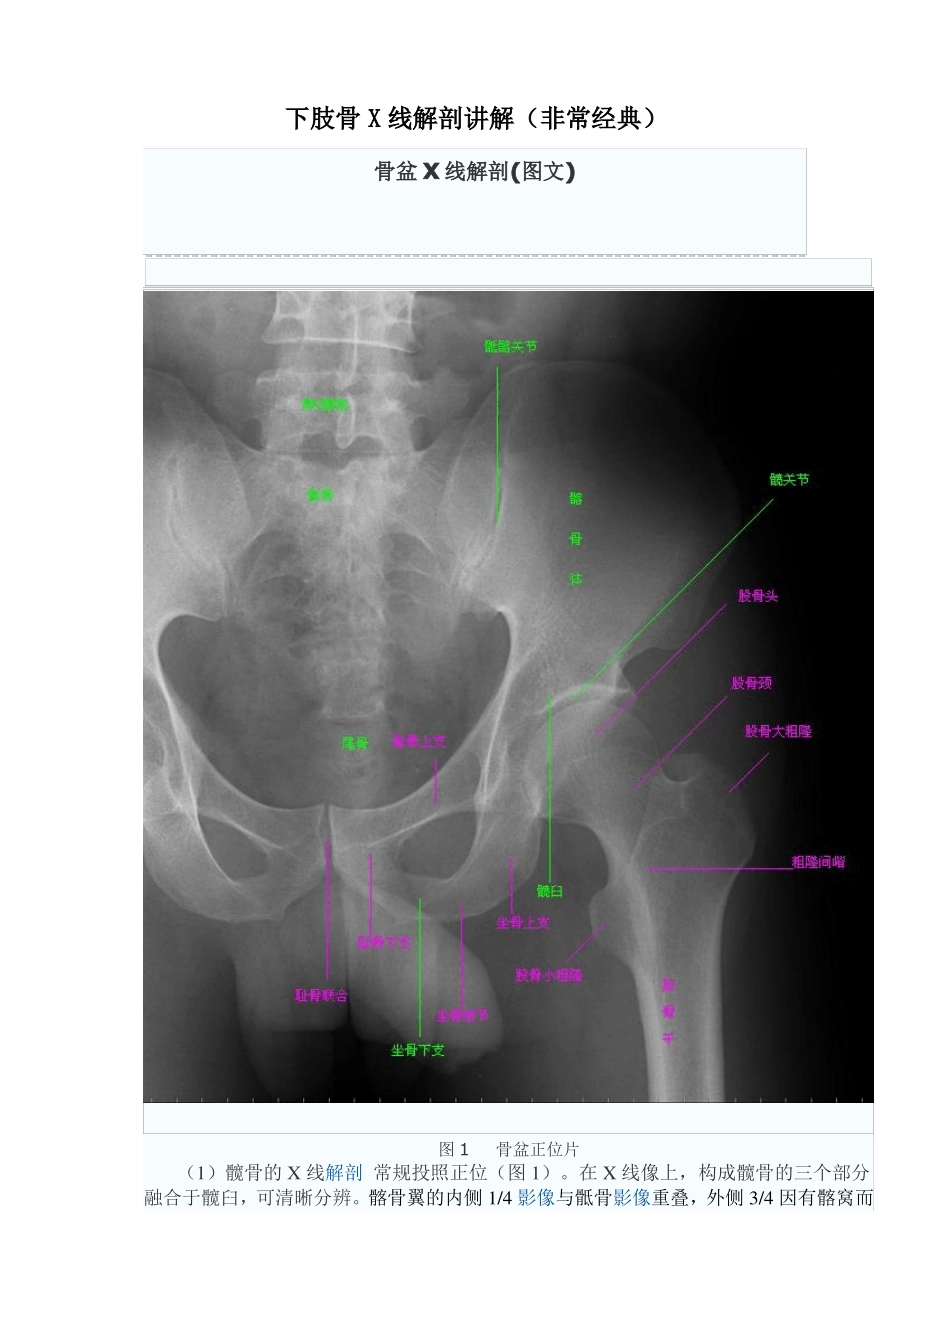

下肢骨 X 线解剖讲解(非常经典)骨盆 X 线解剖(图文)图 1骨盆正位片(1)髋骨的 X 线解剖 常规投照正位(图 1)。在 X 线像上,构成髋骨的三个部分融合于髋臼,可清晰分辨。髂骨翼的内侧 1/4 影像与骶骨影像重叠,外侧 3/4 因有髂窝而较透亮。髂嵴阴影较致密,边缘不光滑,外侧可见髂前上棘影,髂后上棘则重叠于骶骨影内。弓状线及骨盆腔内侧壁形成复合影像,外侧可见弧形的髋臼阴影。髋臼阴影的上段粗而致密,中段较细,它向下绕过髋臼切迹前部的下缘,与耻骨体的内面形成一条“U”形的致密线,称为泪滴线(Koekler 泪滴),泪滴线二脚之间的距离,即髋臼窝的厚度。髋臼内下方的透亮影为闭孔。闭孔影的上界是耻骨上支、外侧界是坐骨体的下份,坐骨结节阴影与其重叠。 坐骨棘的阴影呈三角形突向盆腔。(2)骨盆的 X 线解剖骨盆一般投照前后位,检查骶、尾骨时可加照侧位,检查骶髂关节时应加照 45°斜位,产科骨盆测量另有其特殊投照方法。骨盆前后位片上,骶骨中线应通过耻骨联合。骶髂关节左右对称,关节间隙下半部分可以显示,上半部常投影出模糊双线影。界线的影像在女性呈卵圆形,在男性略呈鸡心形。髂嵴连线影正好通过第 4、5 腰椎间隙。由髂嵴影向外可追踪到骼前上、下棘,由髂前下棘到股骨颈外上缘的连线称髂颈线,用以判定髋关节是否正常。正位片上,可以测量耻骨下角,男性为锐角,女性为钝角。女性骨盆径线的测量,可以采用正位(见图 1)和侧位。正位片上,界线影像最远点连线为入口横径,正常为 12.3cm;两侧坐骨棘连线为中骨盆横径,正常为10.5cm;两侧坐骨结节间距为小骨盆出口横径,正常为 11.8cm。侧位片上,耻骨联合后缘上端到骶骨岬连线为小骨盆入口前后径,正常为 11.6cm;耻骨联合后缘下端和坐骨棘中点的连线延长到骶骨的前缘,为中骨盆前后径,正常 12.2cm;耻骨联合后下缘到骶尾关节的连线,为小骨盆出口前后径,正常 11.8cm。(3)髋关节的 X 线解剖 常规拍摄正位(见图 1)和侧位 X 线片。正位线片上,因髋臼三骨之间以“Y”形软骨相连,融合之前,表现为横行带状透亮影,其宽窄随着年龄变化而改变。年龄越小此透亮带越宽;年龄越大,透亮带变窄,15~17 岁左右消失。股骨头大部套在髋臼内,表面光滑,为致密的细弧线。头的中心偏后下部有一小凹陷,是股骨头凹,有时可投影到股骨头弧线内侧,显示为小环形透亮圈。侧位片上,中央的凹窝是髋臼,呈半圆形的致密线.腕关节及手 X 线解...